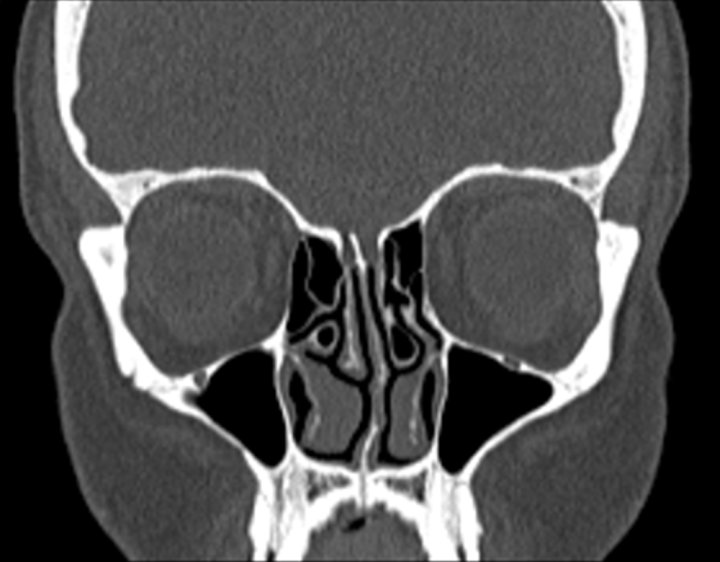

Click any image for labels.